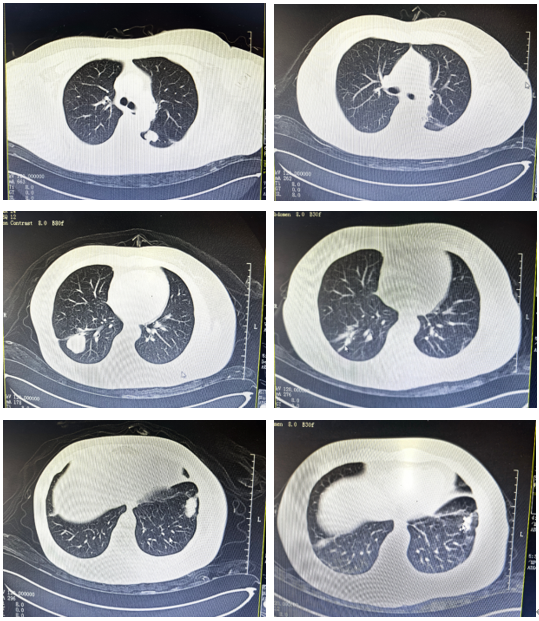

“The doctor said there were many shadows in my lungs—maybe seven or eight,” she recalled.

She traveled to Harbin and Tianjin, visiting hospitals in two cities. Both gave the same diagnosis: lung metastases from cervical squamous cell carcinoma.

“Multiple metastatic tumors in both lungs, close to the right lower pulmonary artery, adhesions with the interlobar pleura and chest wall pleura…”

Based on her condition, the medical team performed two sessions of cryoablation for lung metastases, along with needle biopsies. The biopsy results once again confirmed: metastases from the original cervical cancer.

Ms. Li returned to Fuda and underwent a third cryoablation procedure. However, there were too many nodules, and some continued to enlarge. She subsequently received three iodine-125 seed implantations, which finally reduced the tumors.